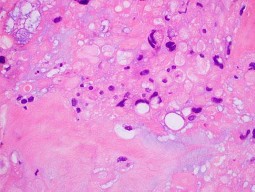

A 35-year-old female is diagnosed with a locally aggressive giant cell tumor of the distal radius. Preoperative administration of Denosumab is planned to facilitate downstaging and joint-salvage surgery. What is the exact mechanism of action of Denosumab in this context?

Explanation

Denosumab is a fully human monoclonal antibody that specifically binds to RANKL (Receptor Activator of Nuclear factor Kappa-B Ligand). By binding to RANKL, it prevents it from interacting with the RANK receptor on the surface of osteoclasts and osteoclast precursors. In Giant Cell Tumor of bone, the neoplastic mononuclear stromal cells express high levels of RANKL, which aggressively recruits and activates the reactive multinucleated giant cells (osteoclasts) that cause bone destruction.